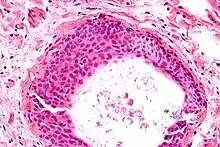

Histologically, there are nests of transitional epithelial (urothelial) cells with longitudinal nuclear grooves (coffee bean nuclei) lying in abundant fibrous stroma.

Micrograph of a Walthard cell nest, the entity Brenner tumours are thought to arise from. H&E stain.